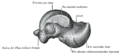

Though irregular in shape, the talus can be subdivided into three parts.

Facing anteriorly, the head carries the articulate surface of the navicular bone, and the neck, the roughened area between the body and the head, has small vascular channels.[2]

The body features several prominent articulate surfaces: On its superior side is the trochlea tali, which is semi-cylindrical,[4] and it is flanked by the articulate facets for the two malleoli.[2] The ankle mortise, the fork-like structure of the malleoli, holds these three articulate surfaces in a steady grip, which guarantees the stability of the ankle joint. However, because the trochlea is wider in front than at the back (approximately 5–6 mm) the stability in the joint vary with the position of the foot: with the foot dorsiflexed (toes pulled upward) the ligaments of the joint are kept stretched, which guarantees the stability of the joint; but with the foot plantarflexed (as when standing on the toes) the narrower width of the trochlea causes the stability to decrease.[5] Behind the trochlea is a posterior process with a medial and a lateral tubercle separated by a groove for the tendon of the flexor hallucis longus. , the lateral of these tubercles forms an independent bone called os trigonum or "accessory talus"; it may represent the tarsale proximale intermedium. On the bone's inferior side, three articular surfaces serve for the articulation with the calcaneus, and several variously developed articular surfaces exist for the articulation with ligaments.[2]

For descriptive purposes the talus bone is divided into three sections, neck, body, and head.

The body of the talus comprises most of the volume of the talus bone (ankle bone). It presents with five surfaces; a superior, inferior, medial, lateral and a posterior:[6]